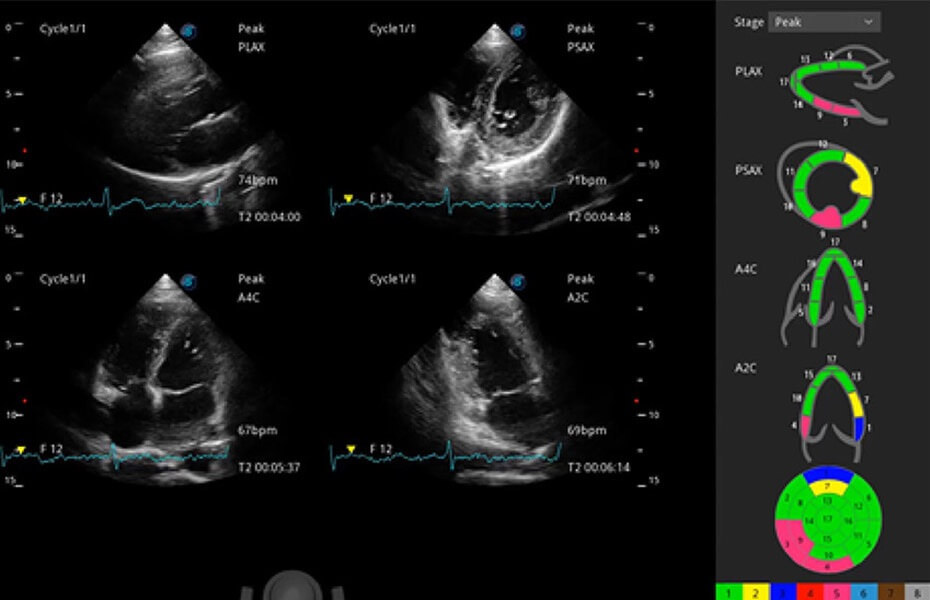

ProPet 60 作為一款高端臺式動物超聲設(shè)備,為動物醫(yī)生的日常診斷提供了一系列貼合動物臨床需求、解決臨床實際問題的高級成像功能。憑借全系列高清探頭,滿足醫(yī)生對腹部、心臟、生殖、淺表、肌骨等成像的所有需求,切實幫助您提升檢查效率,提高診斷信心。